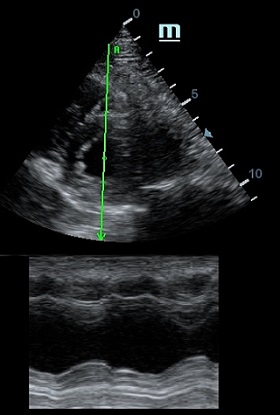

Оценка кооптации нижней полой вены ещё никогда не была такой простой и точной, никаких лишних деталей, просто устанавливаем клипер по анэхогенному участку.